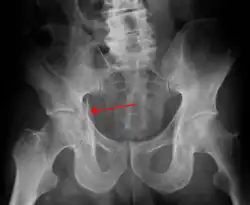

| Acetabular fracture as seen on plain X-ray |

Fractures of the acetabulum occur when the head of the femur is driven into the pelvis. This injury is caused by a blow to either the side or front of the knee and often occurs as a dashboard injury accompanied by a fracture of the femur.[1]

Transverse fracture showing upper iliac fragment, lower ischial and pubic fragment -

Transverse fracture fixed with screws and plate